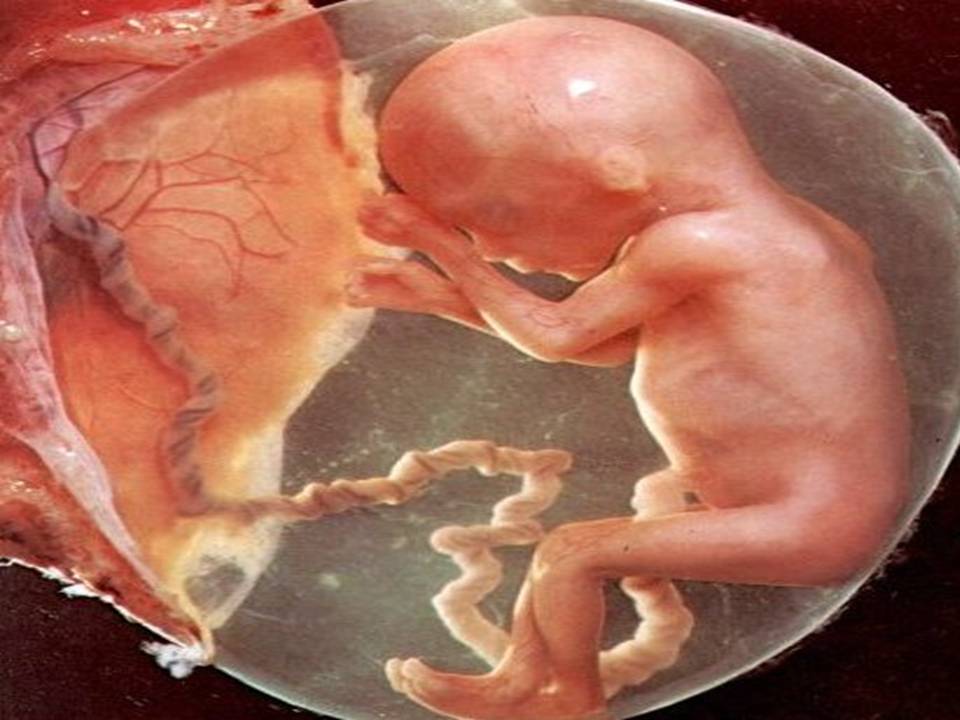

16-17 недель беременности: развитие малыша